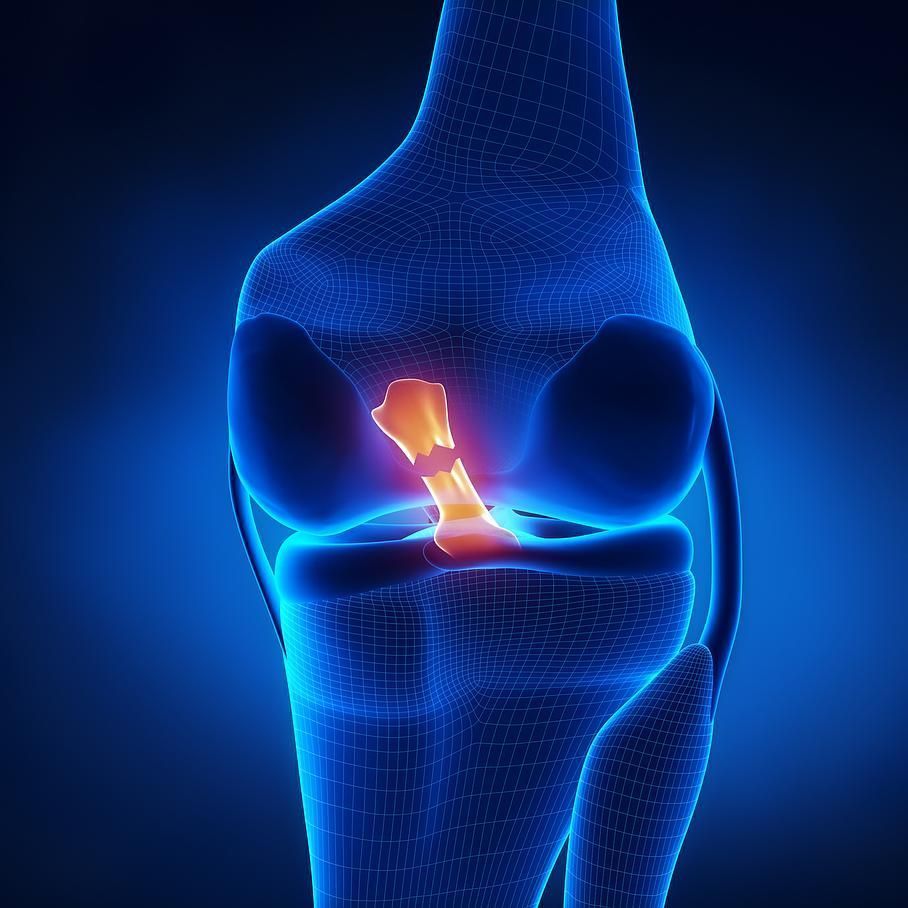

Lésion ligamentaire du genou:

Le genou est stabilisé par quatre ligaments, les ligaments latéraux (médial et latéral) et les ligaments croisés (antérieur et postérieur).

Les lésions du ligament croisé antérieur sont fréquentes et nécessitent un traitement médical ou chirurgical, selon la symptomatologie et l’âge de la personne. Cette chirurgie est faite par voie arthroscopique (mini-caméra et mini-incisions) et reconstruit un nouveau ligament.

Les autres ligaments sont la plupart du temps traités médicalement, bien qu’il faille parfois les opérer.